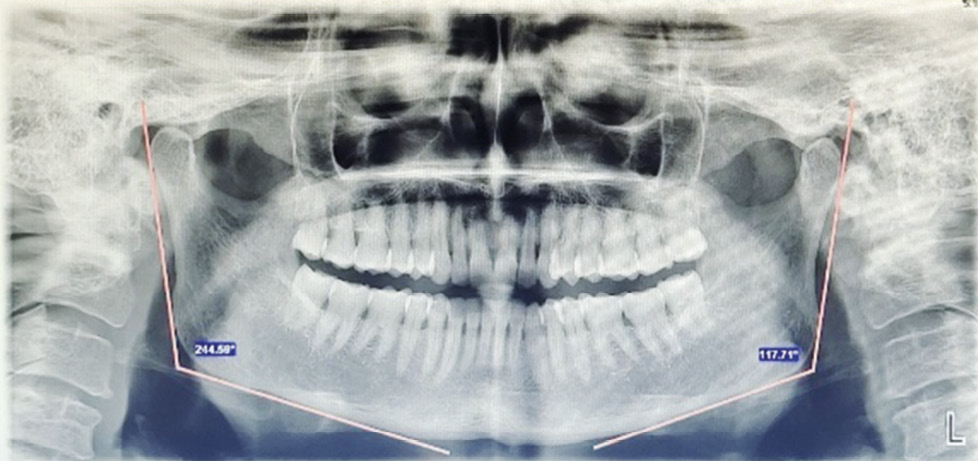

- Ramus length (RL):

Fig. 3. Ramus length bilaterally.

It is calculated by drawing two lines, both parallel to ramus tangent line one at the level of the most lateral image of condyle and the other at the level of the most lateral image of ramus. The distance between these two lines is RL.